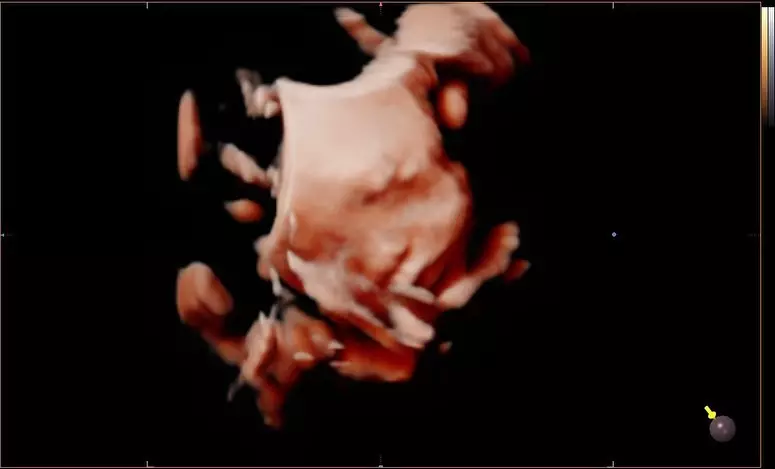

Lucy媽早前貼出細女3D超聲波照,指一樣擁有「豬鼻」。

Lucy 2.0 Sucy已經出世。